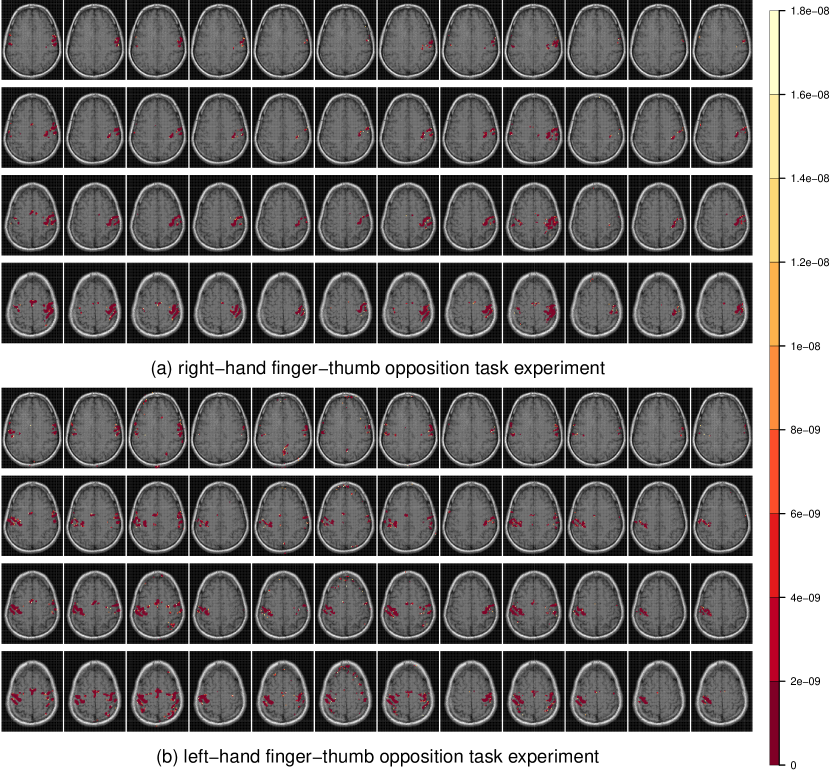

Figure 2: Radiologic view maps of observed p𝑝p-values of activation of the t𝑡t-test of motor function for (a) the right-hand and (b) left-hand finger-thumb opposition task experiments. For each set of experiments, we display radiologic view maps for the 18th, 19th, 20th and 21st slices (row-wise). The twelve replications are represented column-wise from 1 through 12. For each slice, we display the p𝑝p-values of activation for the thresholded voxels using a t𝑡t-test of the motor function for the twelve replications of the finger-thumb opposition experiment performed by (a) the right hand and (b) the left hand of the same right-hand dominant male volunteer. Note the differences in location and extent of activation over the twelve replications. Note, also the substantial more variability in the experiments performed by the subject’s left hand than on the right.

Figure 2 represents the observed p𝑝p-values of activation for slices 18, 19, 20 and 21 (row-wise) over the twelve replications for both the (a) right-hand and (b) left-hand finger-thumb opposition tasks. (All displayed maps in this paper are in radiologic views and overlaid on top of the corresponding T1fragmentsT1\mbox{T}_{1}-weighted anatomical images.) The specific slices were chosen for display because they encompass the ipsi- and contra-lateral pre-motor cortices (pre-M1), the primary motor cortex (M1), the pre-supplementary motor cortex (pre-SMA), and the supplementary motor cortex (SMA). Clearly, there is some variability in the results for the right-hand task. In Figure 2a for instance, all experiments identify activation in the left M1 and in the ipsi-lateral pre-M1 areas, but there is some modest variability in the identified activation in the contra-lateral pre-M1, pre-SMA and SMA voxels, with some experiments reporting very localized or no activation and others having these regions as activated and somewhat diffused in extent. Slices for the left-hand finger-thumb opposition task experiments in Figure 2b, on the other hand, show far more variability, both in location and extent. It is interesting to note that while most experiments identify activation in the right M1, the ipsi-lateral, contra-lateral pre-M1, pre-SMA and SMA areas, they also often show activation in the corresponding left regions. The case of the eighth replication is extremely peculiar. Most of the activity in the four slices are in the left areas and the right areas have little to no activation. This makes one wonder if the naturally right-hand dominant male volunteer had, perhaps unintentionally and out of habit, used his right hand instead of his left in performing some part of the experimental paradigm. In summary, there is clearly far more variability in the left hand set of experiments than in the right hand set. We now assess the reliability in each set separately.

Figures 8a and b display the composite activation maps for the left-hand set by combining all studies and all but the eighth studies, respectively. Figure 8c shows voxels that were differentially activated in the two composite maps. Slices 18 through 21 have more significant voxels in the left areas of (a) than in (b) and fewer significant voxels in the right areas of (a) than in (b). There is therefore increased localization in the identified activation when the eighth study is excluded.